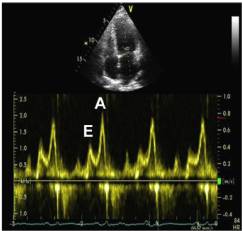

8、二尖瓣口舒张期血流频谱指标1

●Valsalva 动作E/A比值 (1.3—0.6):E/A比值减少≥50%对提示LV充盈压增高具有高度特异性,但是变化幅度较小并不提示舒张功能正常。

●当二尖瓣口血流及二尖瓣环速度测量仍不能确定病人的舒张功能时,Valsava动作还是可以作为一种保留的检查手段。

9、二尖瓣口舒张期血流频谱指标2

20、HFpEF—舒张功能异常分级评估

21、HFpEF—左室舒张功能评估